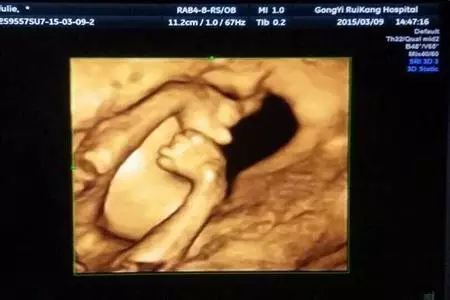

瞧,他对我笑了!看,她在伸懒腰!哦,这个调皮鬼是在做鬼脸吗?

四维彩超不再单纯地感觉宝宝的呼吸和运动,而是可以亲眼目睹他们在妈妈肚子里的一举一动。四维彩超满足了孕妇及家人对宝宝的好奇心理,让准爸爸们更早地对即将诞生的宝宝有了深厚的感情。越来越多的妇产科也允许孕妇家属陪同进入诊室观看栩栩如生的胎儿立体图像,从而提前知道胎儿在母亲腹中的生长发育状况和形态,满足母婴沟通的心理需要,让整个家庭共享生命最初的感动时刻。

四维彩超同时也使医生能够多角度、多方位地观察胎儿在腹中的发育情况,为早期诊断胎儿先天性体表畸开和先天性心脏疾病提供了准确的科学依据。